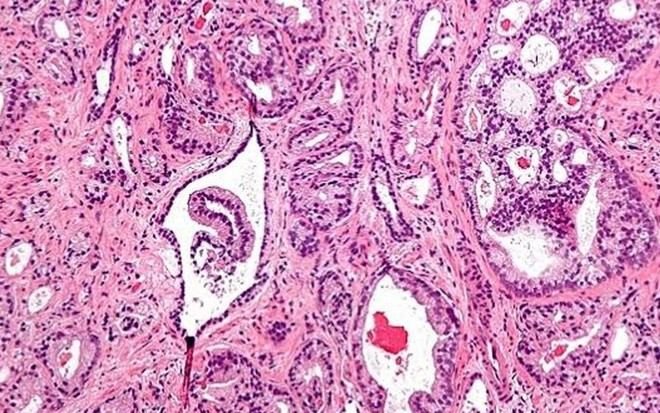

Un reciente estudio realizado por un equipo del Instituto de Salud Carlos III (ISCIII) ha revelado que la exposición al arsénico está asociada con un aumento significativo en el riesgo de desarrollar cáncer de próstata, especialmente en sus formas más avanzadas y agresivas. Este hallazgo se fundamenta en el análisis del arsénico acumulado en las uñas de los pies, en el contexto del proyecto MCC-Spain, uno de los estudios epidemiológicos más amplios sobre cáncer llevados a cabo en España.

Resultados del estudio sobre arsénico y cáncer de próstata

La investigación analizó datos de más de 800 hombres, entre ellos 345 pacientes diagnosticados recientemente con cáncer de próstata y 468 individuos sanos que sirvieron como grupo control. Los resultados indicaron que aquellos hombres con mayores concentraciones de arsénico en las uñas presentan casi el doble de riesgo de desarrollar esta enfermedad comparado con quienes tienen niveles más bajos. Este incremento es particularmente notable en tumores más agresivos y avanzados.